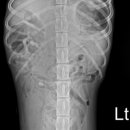

고양동물병원 강아지 저혈당증이 위험한 이유 [위즈동물메디컬센터] 고양동물병원 위즈동물메디컬센터 안녕하세요. 고양동물병원 위즈동물메디컬센터 입니다. 아직 몸도 면역도 충분히 성숙하지 않은 어린...